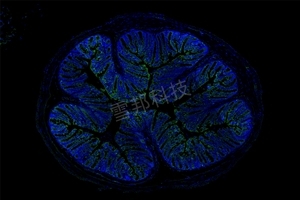

暗场全景扫描

全景扫描是将物质化的玻片标本快速数字化的过程,在荧光模式下能高效、高清晰、全信息的图像采集,是真正脱离显微镜的阅片方式。能长期保存,可满足临床、科研、教学等多种用途。